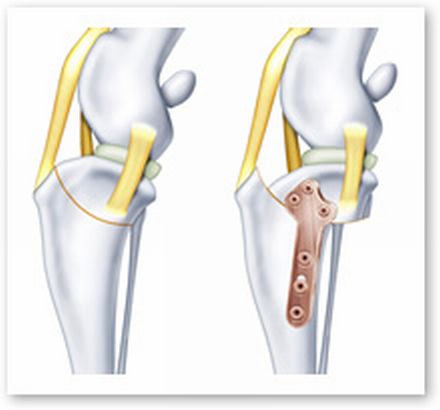

さて、前十字靭帯雄断裂によって、クルーズさんに勧められた治療法は、『TPLO手術(脛骨高平部水平化骨切り術)』

なので、脛骨の先端を切って、大腿骨が滑り落ちない角度に設定、プレートで固定する訳です。